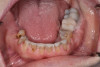

After the restorations were milled, they were sintered and polished for final effect. It was decided that these restorations should not be glazed to avoid the added abrasivity that accompanies this finish to the restoration.22 The patient was then scheduled for temporary crown removal. The final crowns were fitted on the prepared teeth, and the contacts adjusted. The patient reported that she was pleased with the feel and esthetics of the restorations, and the restorations were cemented (Figure 14 through Figure 19).

Fig. 19